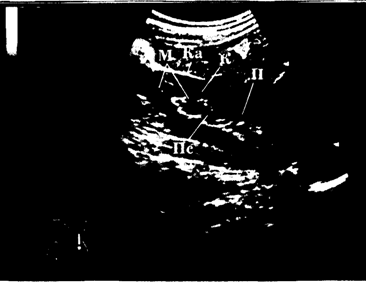

На рис. 18 представлена эхограмма нормальной почки взрослого человека.

![]() | Рис. 18. Эхограмма нормальной почки взрослого обследуемого (продольный трансабдоминальный срез в сагиттальной плоскости). По периферии среза почки визуализируется тонкая гиперэхогенная капсула (Ка), далее – слой паренхимы (П), состоящий из коркового вещества (К) и медуллярного вещества (М), имеющего более низкую эхогенность. В центре среза визуализируется овальной формы гиперэхогенная структура – центральный эхокомплекс (ПС), являющийся суммарным отражением всех элементов почечного синуса |